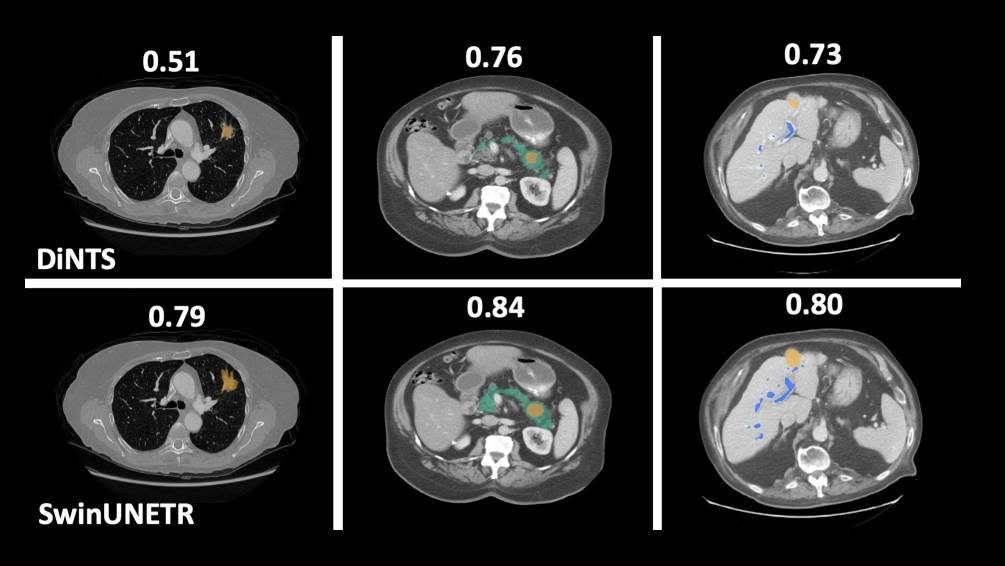

有沒有可能未來我們去醫院後,不用等醫師診斷就能知道自己得了什麼病?這就是"AI數位醫療影像分析"。 透過在判讀醫療影像上結合機器學習,便能輔助醫生診斷、預測疾病、評估療效。身為人工智慧的一個分支,透過分析大量的資料,就能學會自己判斷特定疾病,省略人工判斷每一個病例的環節。這次我們將介紹我們訓練的皮膚疾病辨識模型,並調整參數以提高正確率。